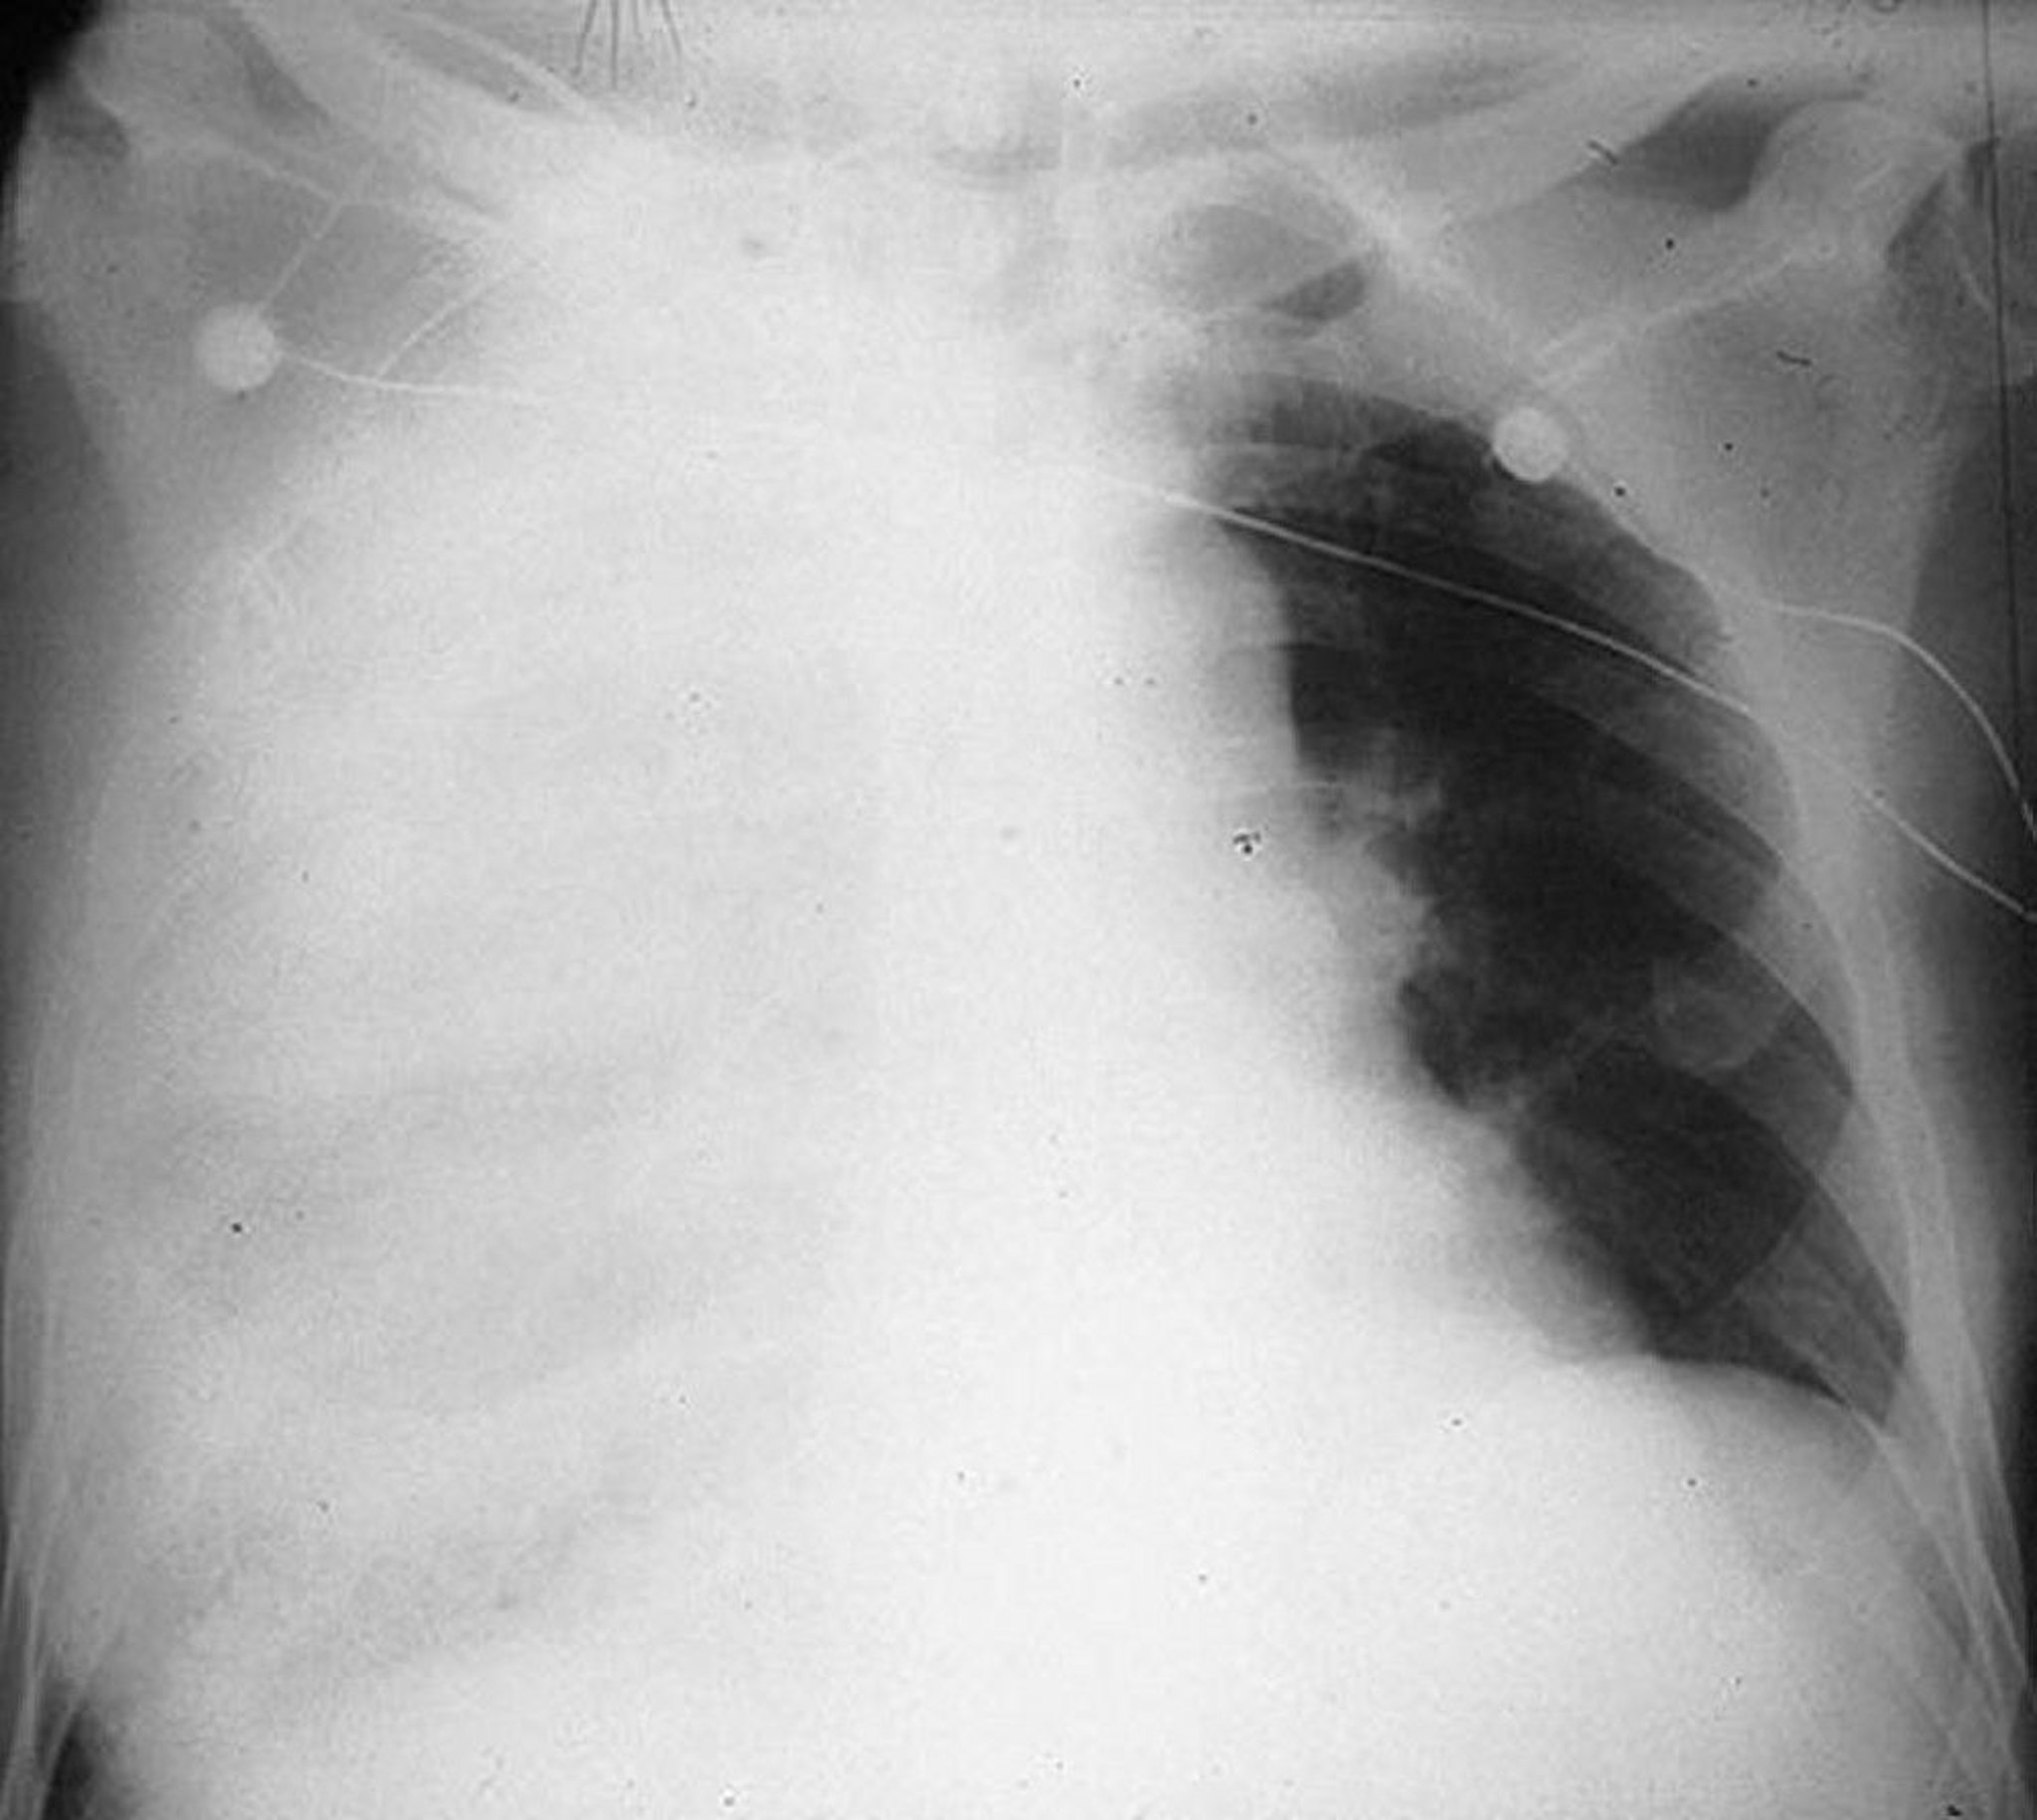

Multilobar Pneumonia

Consolidation of the right upper, middle, and lower lobes in a 64-year-old male with pneumococcal pneumonia.

By permission of the publisher. From Roberts R. In Atlas of Infectious Diseases: Pleuropulmonary and Bronchial Infections. Edited by GL Mandell (series editor) and MS Simberkoff. Philadelphia, Current Medicine, 1996.